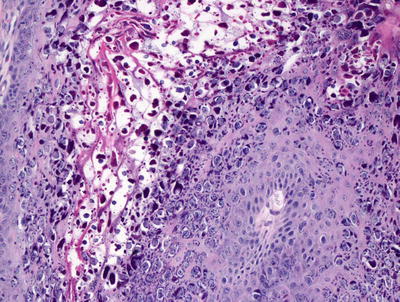

Histologic changes in eczema herpeticum are those of a herpetic dermatitis superimposed upon mild spongiotic dermatitis. Multinucleation, nuclear molding, margination of chromatin, and acantholysis are characteristics of herpes virus infection seen in the epidermis (Figs. 12.14 and 12.15). These changes reflect the nature of the condition that is essentially a generalized infection with herpes virus in the setting of atopic dermatitis. Cowpox and vaccinia infections may demonstrate a similar clinical appearance, but the changes on biopsy vary based upon distinct histologic features specific to the offending viral agent. Similar clinical eruptions have been described in patients with Darier’s disease , Hailey-Hailey disease , rosacea, and mycosis fungoides, the changes are not specific [93–95]. In these cases, histologic evidence of the underlying conditions is apparent when the appropriate clinical sites are biopsied.

Fig. 12.14

A spongiotic epidermis has blistering with acantholysis and viropathic changes in eczema herpeticum/Kaposi’s varicelliform eruption

Fig. 12.15

Viropathic changes of herpes virus infection, including acantholysis as well as nuclear molding and clearing, are seen in eczema herpeticum/Kaposi’s varicelliform eruption